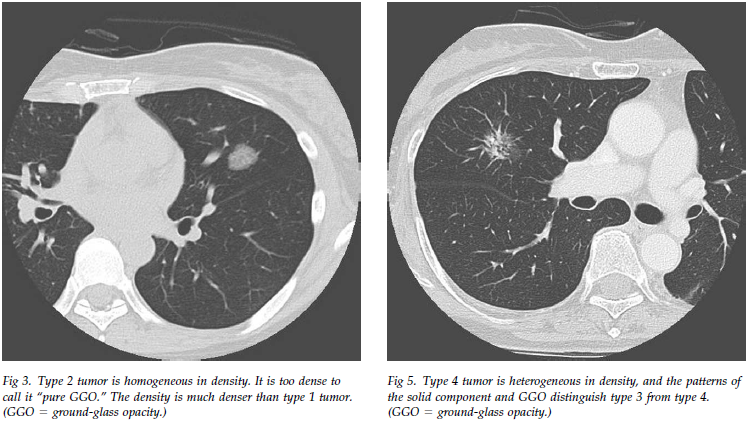

The solid (or consolidation) component was defined as an area of increased oPACIFICation more than 5 mm in diameter, which completely obscured underlying vascular markings.

实性成分被定义为直径>5mm的阴影密度增高影,完全遮盖其下的血管影。

Ground-glass opacity was defined as an area of a slight, homogeneous increase in density, which did not obscure underlying vascular markings.

Semiconsolidation was defined as an area of an intermediate homogeneous increase in density, which did not obscure underlying vascular markings.

截图202305041406278811.png

截图202305041407176329.png